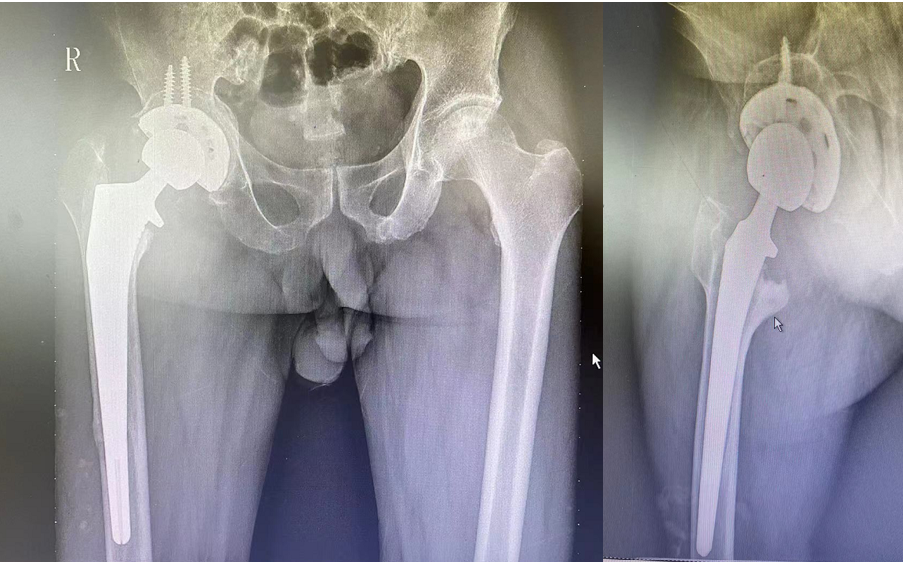

不过庆幸的是该病友手术过程顺利,术中完整取出髋臼杯及股骨柄假体,行生物型髋臼+髋臼底部异体骨植骨+股骨侧生物翻修柄植入,术后患者总体恢复良好出院。

△患者手术后影像学资料